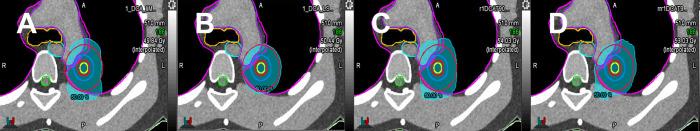

Volumetric modulated arc therapy (VMAT) for lung cancer involves complex multileaf collimator (MLC) motion, which increases sensitivity to interplay effects with tumour motion. Current dynamic conformal arc methods address this issue but may limit the achievable dose distribution optimisation compared with standard VMAT. This study examined the clinical utility of a VMAT technique with monitor unit limits (VMATliMU) to mimic conformal arc delivery and reduce interplay effects while maintaining plan quality. VMATliMU was implemented by applying monitor unit limitations during VMAT reoptimisation to minimise MLC encroachment into target volumes. Using mesh-type reference computational phantom CT images, treatment plans were generated for a simulated stage I lung cancer case prescribed to 45 Gy in three fractions. VMATliMU, conventional VMAT, VMAT with leaf speed limitations, dynamic conformal arc therapy, and constant dynamic conformal arc therapy were compared. Plans were optimised for multiple isodose line prescriptions (50%, 60%, 70%, 80%, and 90%) to investigate the impact of dose distribution. Evaluation parameters included MLC positional accuracy using area difference ratios, dosimetric indices, gradient metrics, and organ-at-risk doses. VMATliMU prevented MLC encroachment into the internal target volume across 60%-90% isodose lines, showing superior MLC accuracy compared with other methods. At the challenging 50% isodose line, VMATliMU had 4.5 times less intrusion than VMAT with leaf speed limits. VMAT plans had better dosimetric indices than dynamic conformal arc plans. VMATliMU reduced monitor units by 5.1%-19.2% across prescriptions. All plans met the clinical dose constraints, with the aortic arch below tolerance and acceptable lung doses. VMATliMU combines VMAT's dosimetric benefits with the dynamic conformal arcs's simplicity, minimising MLC encroachment while maintaining plan quality. Reduced monitor units lower low-dose exposure, treatment time, and interplay effects. VMATliMU is usable in existing planners with monitor unit limits, offering a practical solution for lung stereotactic body radiation therapy.

肺癌的容积调强弧形放疗(VMAT)涉及复杂的多叶准直器(MLC)运动,这增加了对与肿瘤运动相互作用效应的敏感性。当前的动态适形弧形放疗方法解决了这个问题,但与标准VMAT相比,可能会限制可实现的剂量分布优化。本研究探讨了一种带有监测单位限制的VMAT技术(VMATliMU)的临床实用性,该技术可模拟适形弧形放疗并减少相互作用效应,同时保持计划质量。VMATliMU是通过在VMAT重新优化过程中应用监测单位限制来实现的,以尽量减少MLC侵入靶区体积。使用网格型参考计算体模CT图像,为一例模拟的I期肺癌病例制定治疗计划,处方剂量为45 Gy,分三次照射。比较了VMATliMU、传统VMAT、有叶片速度限制的VMAT、动态适形弧形放疗和恒定动态适形弧形放疗。针对多个等剂量线处方(50%、60%、70%、80%和90%)对计划进行优化,以研究剂量分布的影响。评估参数包括使用面积差异比的MLC位置准确性、剂量学指标、梯度度量和危及器官剂量。VMATliMU在60% - 90%等剂量线上防止了MLC侵入内部靶区体积,与其他方法相比,显示出更高的MLC准确性。在具有挑战性的50%等剂量线上,VMATliMU的侵入比有叶片速度限制的VMAT少4.5倍。VMAT计划的剂量学指标优于动态适形弧形放疗计划。VMATliMU在所有处方中减少了5.1% - 19.2%的监测单位。所有计划均符合临床剂量限制,主动脉弓低于耐受剂量,肺部剂量可接受。VMATliMU将VMAT的剂量学优势与动态适形弧形放疗的简单性相结合,在保持计划质量的同时最大限度地减少了MLC侵入。减少的监测单位降低了低剂量照射、治疗时间和相互作用效应。VMATliMU可在具有监测单位限制的现有计划系统中使用,为肺部立体定向体部放疗提供了一种实用的解决方案。